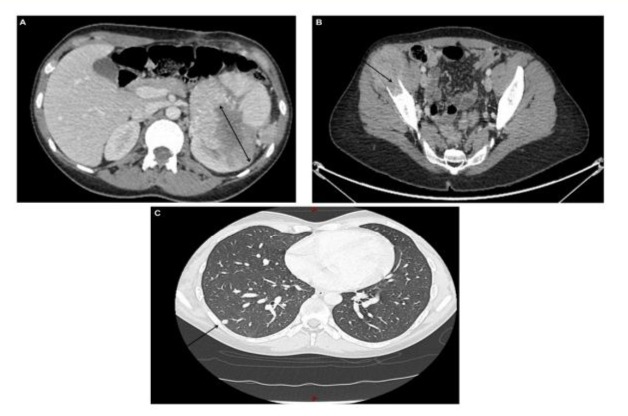

In October 2019, a 27-year-old female patient, an unexpected and acute pain in the right hip bone. Radiographic imaging showed a lytic lesion of the right iliac wing. Blood test showed elevated CRP (C-reactive protein), LDH (Lactate dehydrogenase) and fibrinogen, thrombocytosis and inflammatory anemia. She works as a laboratory technician in the food industry, where she has been exposed to solvents but observed the necessary precautions. The clinical exam did not reveal neither ascites, nor hepatomegaly, or neurological signs. Computed tomography (CT) showed a large mass in the left kidney, secondary bone lesions (left clavicle, T12 and T5 vertebrae without a direct risk of compression and in the right iliac wing), an adjacent left adrenal lesion and at least six pulmonary nodules. (Figure 1A-C). Biopsy of the iliac lesion found a sarcomatoid carcinoma with a renal origin (Positive PAX 8 compatible with a clear cell renal cell carcinoma with a sarcomatoid differentiation (IMDC 4)). No TFE3 expression or loss of BAP1 expression, with loss of SDHB expression were reported (Figure 2).

Figure 1: A CT total body base line revealed a primary renal lesion measuring 10 cm (A), a lytic lesion of the right iliac wing (B) and multiple pulmonary nodules (C).